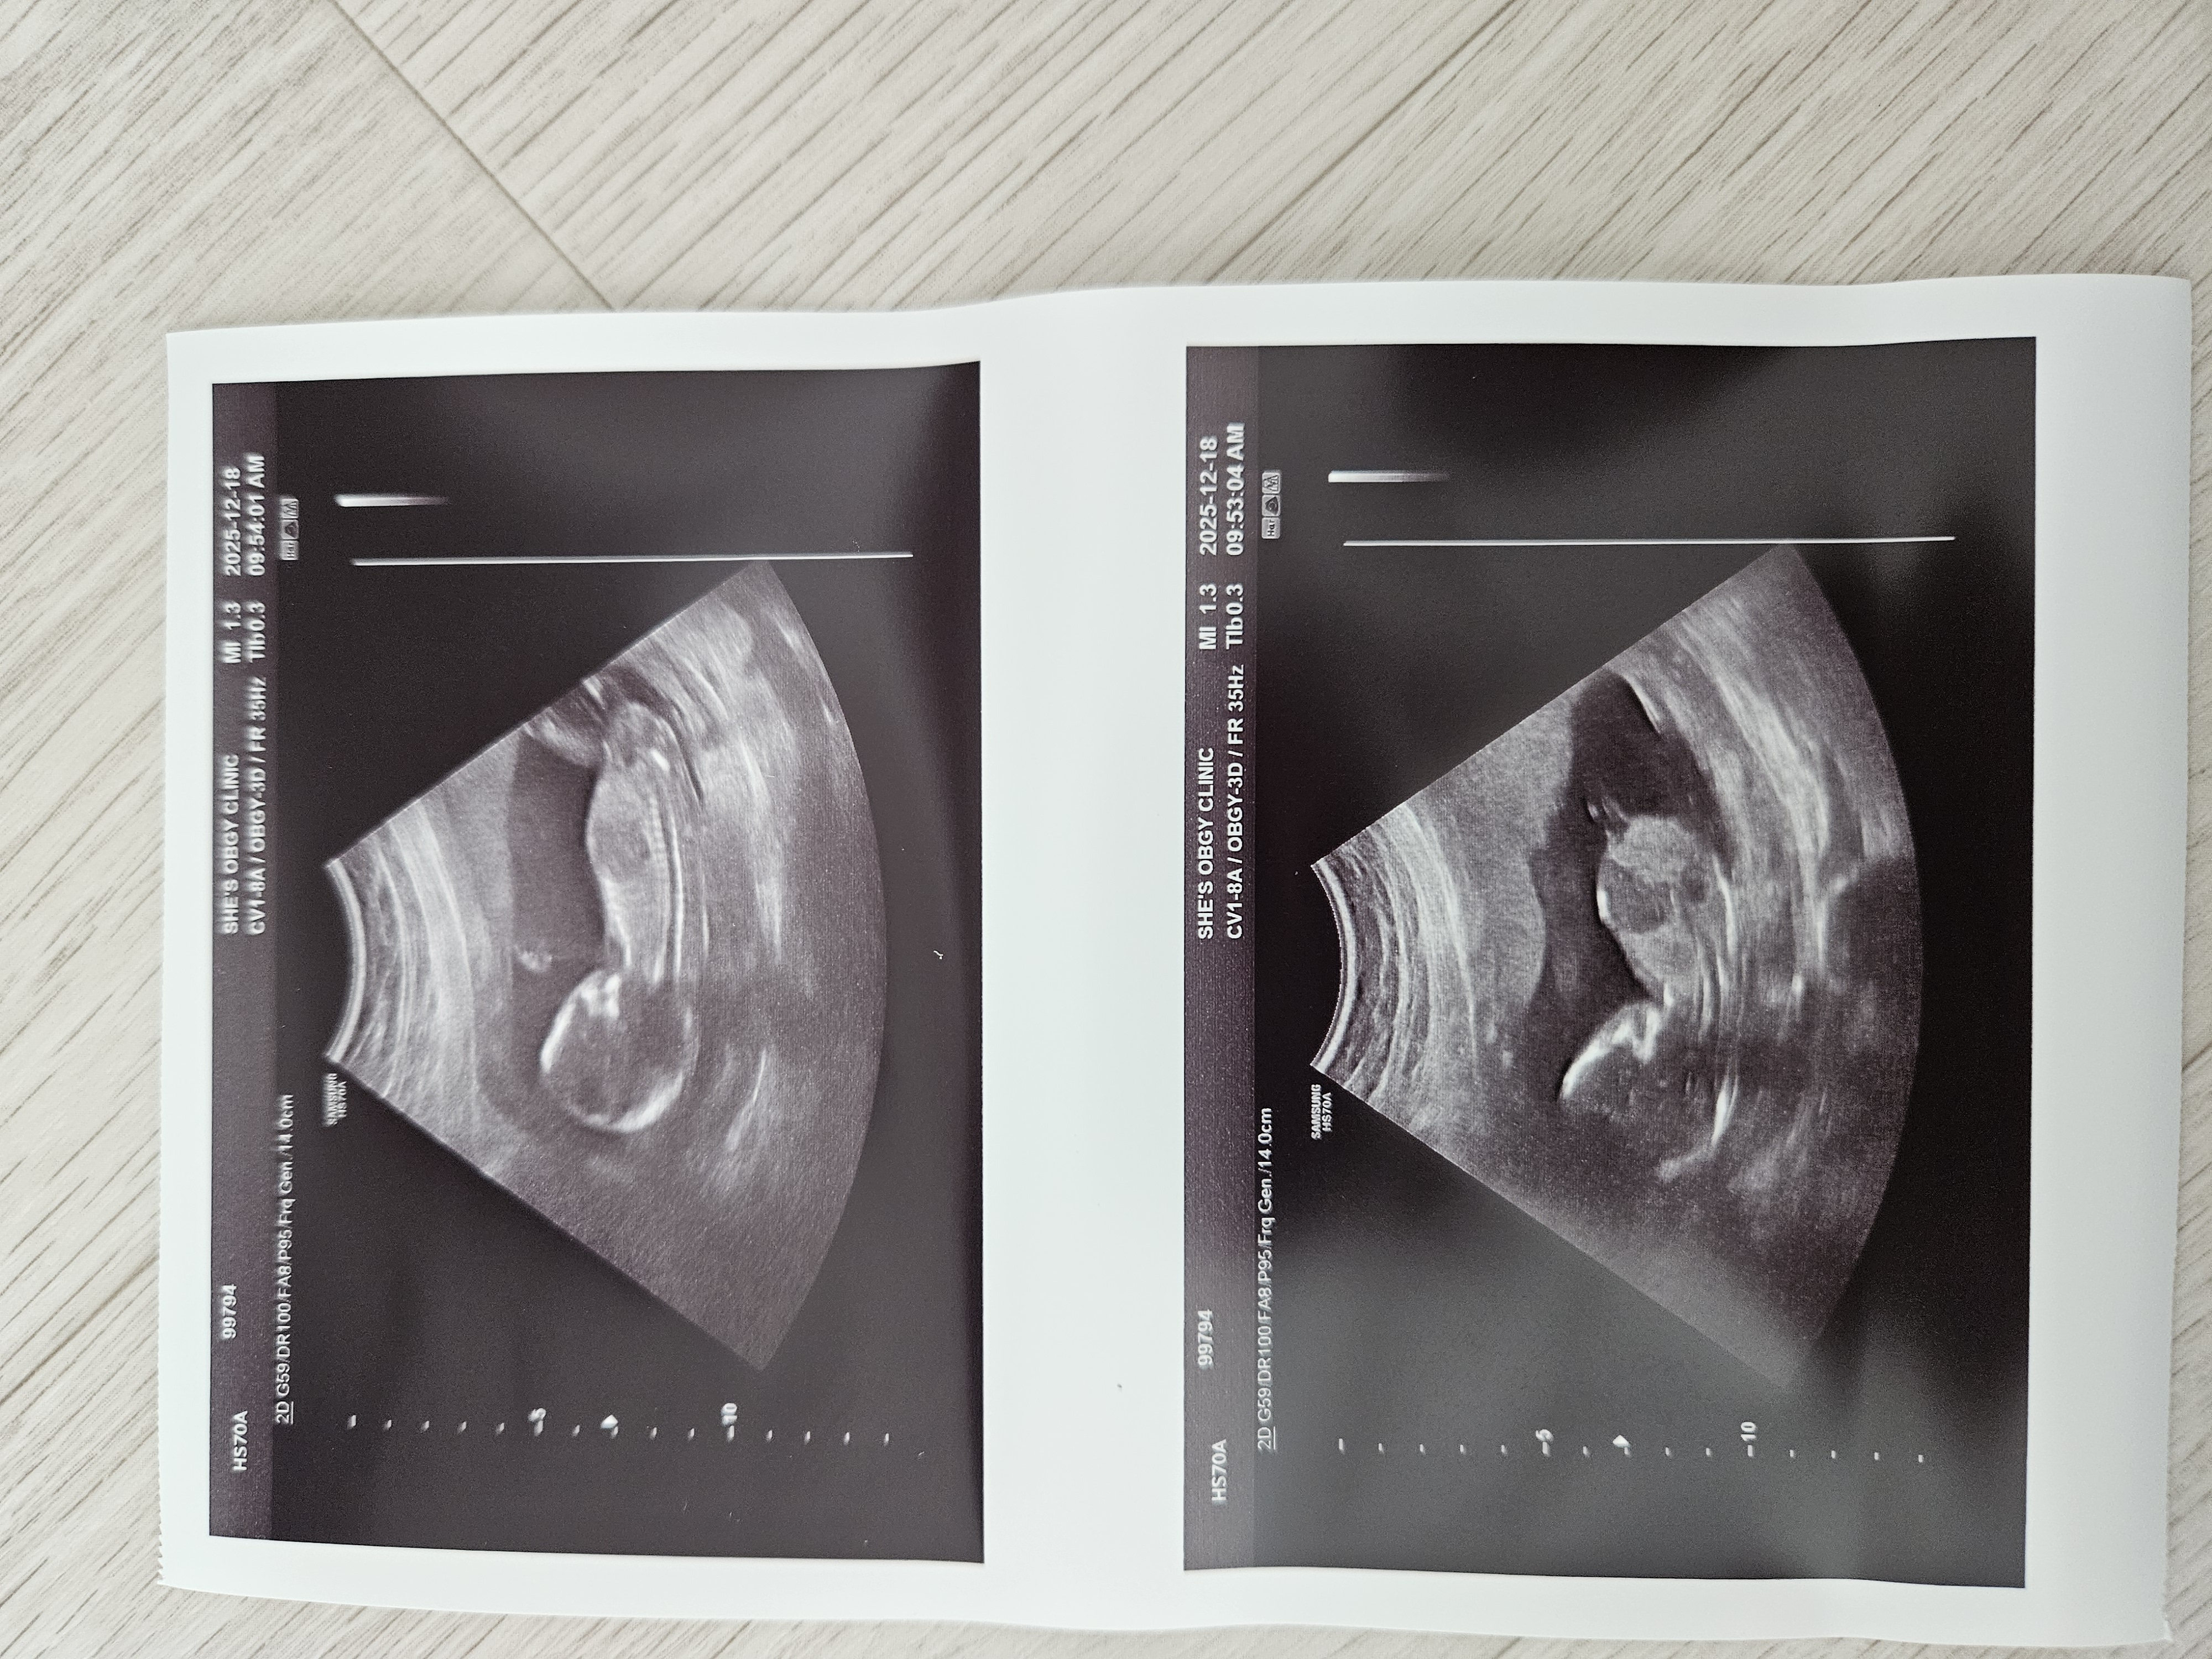

성별 반전이 있을까요?ㅠㅠ

딸이길 바랬는데.. 4주뒤면 반전이 있을지 빼박일지ㅠㅠ

12주부터 존재감뿜뿜이면 4주뒤에 바뀔확률이거의없어용...ㅠ 참고로 전 아들맘입니다

저도그럼 아들둘맘이 되는거네요ㅠ 건강하게 낳아서 이쁘게 잘키워봐요^^